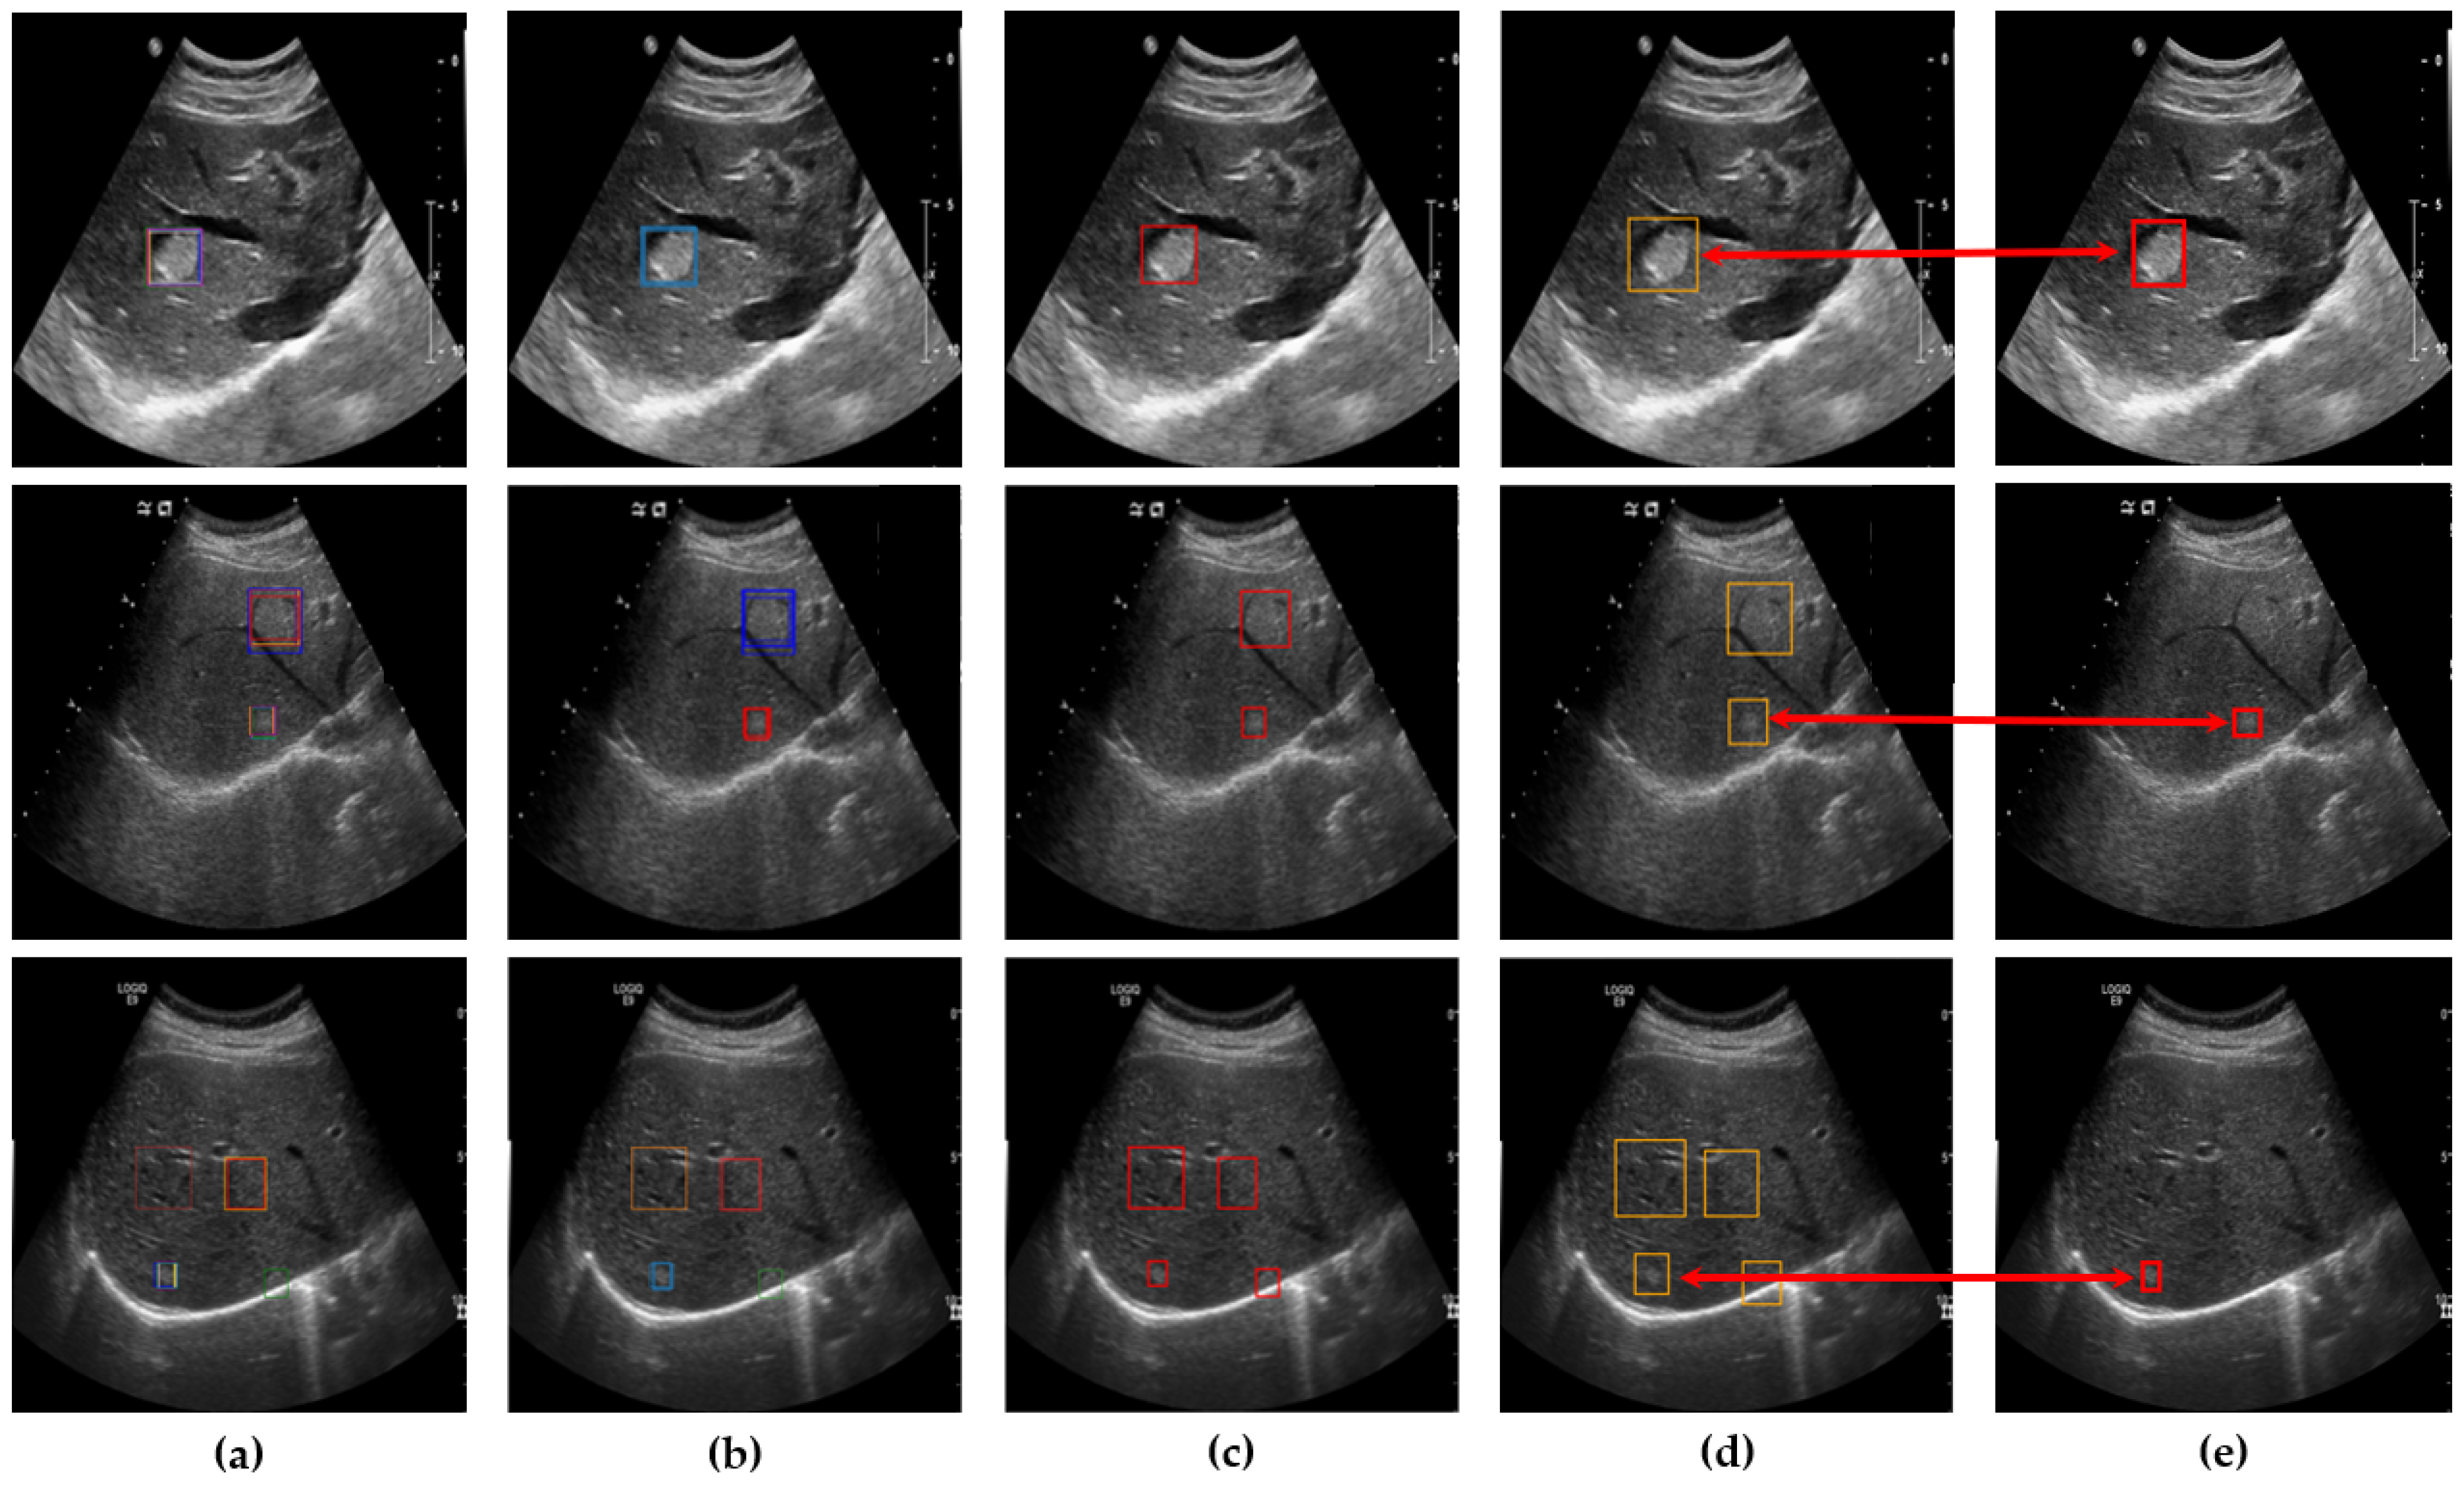

To evaluate the accuracy of lesion detection after applying clustering, SM-WBF, and padding, a novel measurement method was introduced. The primary goal was to ensure that all regions suspected of being lesions were identified, minimizing the chances of missing any lesions. As illustrated in Figure 5, all detected lesion-suspected regions were compared with the ground truth, and if at least one box matched, the detection was considered successful. A match was determined by comparing the IoU between the detected box and the ground truth box including padding. An IoU of 0.9 or higher was used as the threshold for a match, ensuring high precision in detection evaluation (Figure 6).

Figure 5. Determination of bounding boxes using clustering, SM-WBF, and padding. (a) All bounding boxes detected by the ten networks. (b) Clustering of bounding boxes into four regions using DBSCAN. (c) Application of SM-WBF with SoftMax weights to the clustered regions. (d) Addition of padding to the bounding boxes in (c).